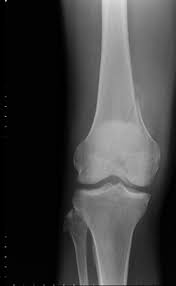

Medial Femoral Condyle, Eorthopod Patient Education : If there is a fracture (break) in part of the condyle, this is known as a fracture of the femoral condyle.. Juvenile ocd lesions have a better healing prognosis than adults. Sagittal plane fracture of the medial femoral condyle. This adaptable graft option is most commonly used with oats or shell techniques to restore cartilage in the knee, but can also be used to for cartilage restoration of other joints. This is associated with a positive bone scan and, frequently, a radiolucent lesion in the subchondral zone. Of the six patients who had suffered an isolated fracture of their medial condyle, four of the patients had their fractures diagnosed on the first visit.

Use your time efficiently and maximize your retention of key facts and definitions with study sets created by other students studying medial femoral condyle. Given its location, these are also the easiest cartilage defects to repair. Normal irregular ossification of the femoral condyles was present in 66% of the boys and 44 % of the girls 1 in a review of knee radiographs of 147 healthy, asymptomatic children between the ages of 3 and 13 years. The flap is marked by identifying the vascular plexus on the medial condyle and incorporating a component of the network in the flap. Primary osteonecrosis of the femoral condyle shares several features with insufficiency fractures, including predominance in elderly women with factors responsible for mechanical stress (varum, obesity, trivial trauma), mechanical pain, and increased radionuclide uptake. The femoral condyle allograft has been used for resurfacing cartilage defects with mature hyaline cartilage for several decades, with very high success rates. Osteonecrosis of the medial femoral condyle presents as a sudden onset of pain on the medial side of the knee. An articular cartilage injury, or chondral injury, may occur as a result of a pivot or twist on a bent knee, similar to the motion that can cause a meniscus tear.

Chondral injuries may accompany an injury to a ligament, such as the anterior cruciate ligament. Your knee mri will often show a: Schatzker i tibia plateau fracture. Osteonecrosis of the medial femoral condyle presents as a sudden onset of pain on the medial side of the knee. Normal irregular ossification of the femoral condyles was present in 66% of the boys and 44 % of the girls 1 in a review of knee radiographs of 147 healthy, asymptomatic children between the ages of 3 and 13 years. However, two of the patients had one or more fractures missed when they first presented. A bone fracture at this location is termed a femoral condyle fracture. According to the hospital for special surgery, the medial femoral condyle is the inside of the knee, and health issues dealing with it can be treated.